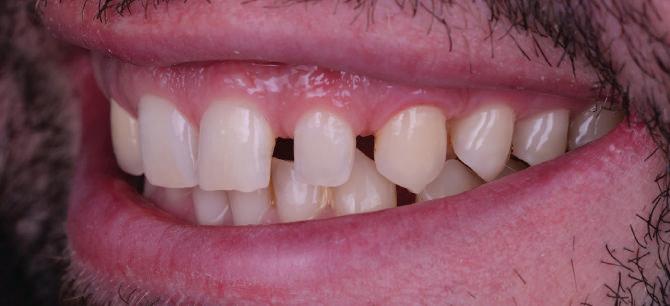

Пациентът постъпи в клиниката с молба за тотална рехабилитация на усмивката. Той не харесваше централ ните си резци, които според него бяха твърде къси и квадратни. Имаше раз стояние от медиално и дистално на латералните му резци. Друго сериоз но оплакване бе свързано с металоке рамичната корона на зъб 12, която бе жълтеникава и неестетична, като цяло не харесваше вида на венците си и както самият той се изразяваше, „вижда се прекалено много от венците при усмивка“.

След диагностиката бяха направени екстра- и интраорални снимки, както и рентгенографии; професионалното почистване бе от изключителна важ ност, бяха дадени и инструкции за лич на орална хигиена. Бе направено интра орално сканиране с Medit i500. Цялата тази информация бе използ вана в приложението Smilecloud за 2D биометричен дизайн. В приложението са налични естест вени форми на зъбите и щом бяха под брани зъби и бе направен дизайн

библиотеката на Exocad. Струва си да се отбележи, че 2D дизайнът от Smile Cloud бе спазен до последния детайл в Exocad smile creator с цел да се създаде 3D obj файл със зъбните форми. След като естетичният дизайн бе готов в model creator модула на Exocad, адитивен 3D мок-ъп модел бе експорти ран и принтиран от принтер Formlabs 3. Моделът бе използван за направата на силиконов водач, за да се изготви мо тивационен мок-ъп в устата на паци ента и да се оценят естетичните па раметри. След като пациентът одобри вида на усмивката си, мок-ъпът бе използван за финализиране дизайна на усмивка та. Мок-ъпът бе използван също така като водач по време на мекотъканна та хирургия, както и при препарация на зъбите.

Препарираните зъби бяха импорти рани в Exocad и насложени върху ес тествените форми от биометричния дизайн, като така стана ясно дали зъ бите са били препарирани коректно. По този начин зъболекарят и зъботехни кът работят в една и съща екосистема и резултатът е оптимален. С короната се справихме чрез диги тална редукция на циркония в Exocad, като по този начин на практика създа дохме циркониево кепе, след което про изведохме фасета от IPS Empress Cad Multi. Кепето от Katana Zirconia на зъб 12 с букално послойно нанесена керами ка бе фрезовано (послойното нанасяне бе направено, за да се подобри връзката и да се осигури адхезивно циментиране на фасетата към циркониевото кепе, както и за да се напасне цветът към този на съседните зъби). При първото сканиране регистрирах ме цялата горна зъбна дъга, така че, ко гато се наложи да сканираме повторно, бе изтрит и сканиран наново само зъб 12, тъй като венците не бяха отдръп нати при второто сканиране.

НА

рентгенографии. Инициална терапия и професионално почистване. Интраорално сканиране с цел диги тално планиране. Регистрация и 3D ориентиране на ок лузалната равнина на горна и долна челюст в пространството. 2D дигитално планиране и дизайн на усмивката посредством приложение то Smile Cloud. 3D дигитално планиране и дизайн на функционалните и естетичните па раметри. 3D дигитален дизайн и адитивен мокъп на горна челюст. 3D принтиране и мок-ъп модели. Мотивационен мок-ъп. Фини корекции за постигане на фи налния дизайн. Мекотъканна хирургия с мок-ъпа като водач Препарация през мок-ъпа, използвай ки дизайна като водач за финалната препарация в Exocad. Циркониево кепе ще бъде циментира но с цел адхезивно залепяне на фасе та на края. Кепето има същия цвят като този на съседните зъби, за да може фасетата да се впише перфект но в цялостната усмивка. Изработване на 12 IPS Empress Cad Multi фасети с послойно нанесена ке ТОТАЛНА РЕХАБИЛИТАЦИЯ НА УСМИВКАТА С ИЗЦЯЛО ДИГИТАЛЕН ПРОТОКОЛ Д-р Калин Маринов и зт. Стефан Петров рамика букално върху зъбните препа рации и върху първичното циркони ево кепе (има възможност за ецване и адхезивно

Една седмица след препарацията на зъбите и циментирането на цирко ниевото кепе бяха изработени 12 IPS Empress Cad Multi фасети. Макро- и микротекстурата на фасе тите бяха направени на ръка, след кое то бяха нанесени 3D характеризации с боички, а полирането отново бе напра вено ръчно, за да им се придаде естест вен и естетичен вид. Предизвикателството тук беше короната да има същите оптични характеристики като тези на остана лите зъби при естествена светлина, през поляризационен и флуоресцентен филтър. 3D принтерът бе Fromlabs, софтуерът за фрезоване – Mill Box, а фрез апаратът –imes icore CORiTEC 350i. В крайна сметка постигнахме ес тествен вид на усмивката с натурал на зъбна морфология при изцяло диги тален протокол, при който дизайнът бе направен първоначално и през всич ки етапи на лечението се придържахме към него до самия край Излишно е да отбелязваме, че всички сме удовлетворени от постигнатото! Преди След Победител в категория „Клиничен случай с изцяло дигитален протокол“ в конкурса „Усмивка на годината 2022“

11Dental Tribune Bulgarian Edition / октомври 2022 г. Преди лечението Фиг. 1 Фиг. 2 Фиг. 3 Фиг. 4 Фиг. 5 Фиг. 6 Фиг. 7 Фиг. 9 Фиг. 10 Фиг. 11 Фиг. 8 Фиг. 12 Фиг. 13